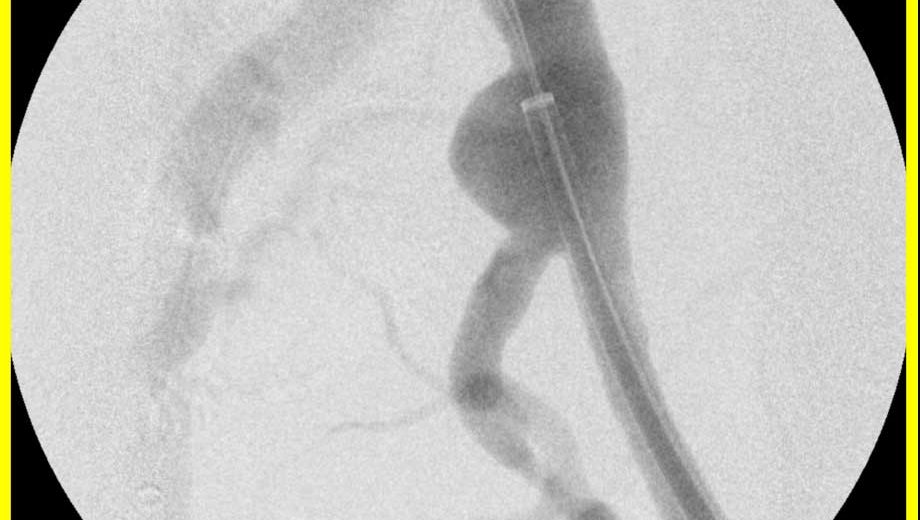

Hier sehen Sie die endovaskuläre Behandlung eines Aneurysma der A. iliaca communis links unter Erhalt der A. iliaca Interna links.